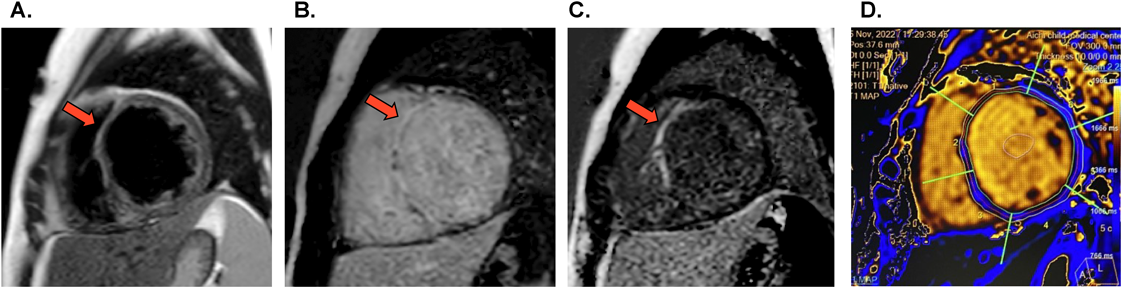

Pediatric Cardiology and Cardiac Surgery 40(2): 91-102 (2024)

Fig. 3 Cardiac MRI findings in our case of persistent chronic active myocarditis 4 months after onset of fulminant myocarditis. These findings met the diagnostic criteria for acute myocarditis according to both the 2009 and 2018 Lake Louise Criteria

A) T2-weighted black blood imaging. Arrow indicates regional high T2 signal intensity. B) Early gadolinium enhancement imaging. Arrow indicates positive finding of the enhancement. C) Late gadolinium enhancement imaging. Arrow indicates positive finding of the enhancement. D) T1 mapping showed prolonged native T1 values (mean 1251 ms; reference value 1050+/−50 ms) and extracellular volume fraction increased to 46.6%.

近年の心臓MRI技術の進歩は目覚ましく,心筋炎診療における心臓MRIの位置付け,重要性が非常に高くなってきている.2009年に心臓MRIによる急性心筋炎画像診断基準(Lake Louise Criteria)16)が示され,その後,心筋固有の信号値を示すT1/T2マッピングや細胞外容積分画を用いた心筋傷害評価法のエピデンスが蓄積され,2018年にLake Louise Criteriaが改訂された17).心筋浮腫を示すT2を基準とした画像の判定基準(T2強調像またはT2マッピングで陽性所見),および心筋傷害を示すT1を基準とした画像の判定基準(ガドリニウム遅延造影LGE, T1マッピング,細胞外容積分画のうち1つ以上の陽性所見)をともに満たせば心筋炎と画像診断できる(Table 2).しかし,発症からの時間経過とともに心臓MRIによる心筋炎診断能は低下するため,発症後2~3週間以内に行うことが望ましい.Lake Louise Criteriaはあくまでも「急性」心筋炎の画像診断基準であることに留意する必要があるが,慢性活動性心筋炎においてもLake Louise Criteriaを満たす例がある(Fig. 3).

心臓MRIによる予後評価として,生検で確定診断したウイルス性心筋炎において,発症5日以内に施行した心臓MRIでのLGE陽性例は陰性例に比してその後の心臓死,突然死が有意に高いことが報告されている18).また,発症6カ月後の心臓MRIで心筋浮腫消失後もLGEが残存する例,初期よりもLGEの範囲が拡大する例は予後不良との報告もある19).急性心筋炎の診断,病態モニタリング,予後評価を行う目的での心臓MRI撮影は推奨クラスIである.